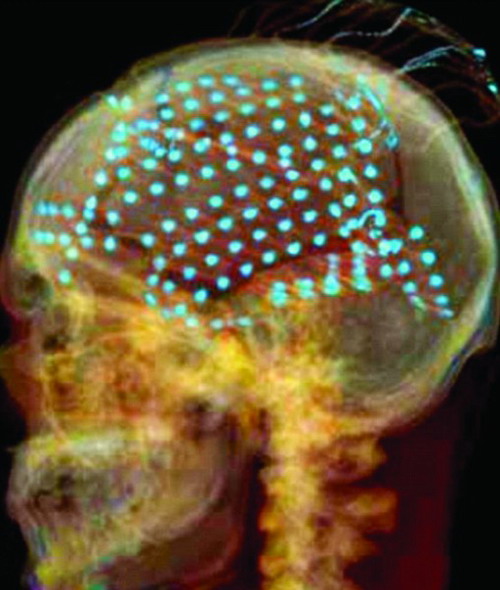

图2 颅内电极埋藏后显示电极位置 颞叶癫痫放电的传导多是在同侧,但有时也可不经过同侧皮层,而通过海马背部联合直接向对侧传导”。所以在确定癫痫起源侧别时,多需双侧相同部位对称安装相同的电极,并常配合皮层电极使用,即同时安装海马深部电极和颞叶皮层电极。对于双侧颞叶存在致痫灶,尤其是双侧颞叶独立起源的患者,因该类患者只有一次手术机会,应极为慎重。对于单侧颞叶癫痫患者,手术疗效好,应首选手术。但是,双侧独立起源的颞叶痫灶,手术效果尚不能肯定,应根据患者情况慎重决定是否手术以及手术方式,必要时放弃手术或选用其他治疗方法。 由于颅内深部电极内有一金属导芯,放入电极后,拔出导芯时应仔细,尽量避免撤除导芯引起电极移位。颅内深部电极植入亦可用于颞叶之外的深部电极植入,例如下丘脑错构瘤等病例。 临床中还经常遇到影像学阳性发现与VEEG不一致的情况,因不能确定棘波是否为病灶传导所致,虽然行颅内电极植入,但仍有影像学病灶与iVEEG不一致的情况,此时应反复考虑,慎重决定手术方式。 虽然颅内电极植入出现并发症的概率不高,但仍应高度警惕。严重并发症有脑脓肿、硬膜外血肿、脑脊液漏、硬膜下出血等。我们体会,在钻孔放置条状电极时,动作应轻柔,如果放置过程中遇到阻力,疑为桥静脉时,为避免引起出血,应调整放置方向;在放置栅格状电极时,应避免脑脊液流失过多,硬膜应严密悬吊,以防止硬膜外出血。同时避免放置电极过多,密度过大。因脑脊液漏是最常见的并发症,所以皮下组织和皮肤应严密缝合,以减少脑脊液漏的发生。此外,电极应固定于头皮以防止电极脱出。 总之,在癫痫外科中,iVEEG具有独特而不可替代的实际应用价值。对于影像学检查阴性的病例,当其他无创检查也不能提供准确的定位信息,iVEEG便成为惟一的选择。但是,iVEEG仅能反映电极局部的神经电活动,电极数量以及能够监测到的皮质范围非常局限,所以只有当术前评估能够将致痫灶定位在一定的范围内,或已经基本明确致痫灶的部位而要进一步排除其他某个可疑部位时,才应考虑埋置颅内电极。 近年来,随着对脑网络与致痫网络研究的逐渐深入,立体脑电图技术逐渐得到认可和推广。立体脑电图(stereo—electroencephalography。SEEG)是一项有创检查技术,其形成于上世纪50年代的法国Saint Anne医院。1966年Baneaud和Talairach两位教授基于SEEG技术,提出了致痫灶的定位应以临床症状一脑电生理一脑内解剖结构为理论依据的临床思路,成为当前指导多数欧洲国家在开展SEEG时所遵循的判定方法和理论基础。 与ECoG比较,SEEG的优势在于无需开颅手术。可同时对脑深部结构如海马、内嗅区、扣带回、岛叶、脑回中的皮层以及脑深部病变如脑皮质发育不良(focal cortical dysplasia,FCD)进行电生理监测,而后者只能监测手术暴露脑皮层表面的放电特征,存在监测上的空间局限性(已知近2/3的大脑皮层位于沟回内)。SEEG的独特之处还表现为可研究癫痫发作期和发作间期的症状与电生理及其传播途径的关系,即解剖上点对点的分析、症状学上秒对秒的观察,例如SEEG对于内侧颞叶癫痫杏f-核所起作用的研究,岛叶癫痫症状与电生理相关性的研究等。 与DE比较,SEEG在技术与理论上存在明显的区别SEEG非对称性放置,且多数情况下放于一侧半球,主要用于定位致痫灶和研究其传播途径。而深部电极常常对称性放置,更多地用于定侧别。其关注的足脑深部结构靶点的异常放电,而不能完成整个电极(从皮层、脑自质和中线结构的同时监测)。另外,由于SEEG采用Talairach立体定向头架,钻孔直径小,避免了脑脊液的流失,减少感染发生的概率,因而放置时间可更长一些,有利于电生理监测。 SEEG指征:(1)MRI阴性患者,发作间期或发作期脑电图与临床症状部分或者完全不吻合时。(2)MRI阳性患者,发作间期或发作期脑电图、临床症状和致痫灶范围波及到病灶以外的区域。(3)MRI阴性或阳性,癫痫发作表现与发作期EEG的放电侧别不符,或发作期EEG显示迅速波及对侧半球时。(4)MRI、发作期EEG和发作期表现证实致病灶涉及到功能区时,为制定手术方案、定位功能Ⅸ部位和评估手术风险时。(5)MRI显示病变范围广泛、涉及一侧或双侧半球时.发作期EEG和临床表现存在多个潜在的致痫灶可能或涉及到双侧半球时。 SEEG是临床症状一电生理一解剖的结合。其基础是以临床表现为依据,按发生顺序逐步分析癫痫发作时临床症状与脑内放电之间的关系、累积的解剖部位。在定位致痈灶的过程中,SEEG遵循的方法是:(1)对癫痫发作期的整个临床表现过程进行分析分类。(2)将每次发作与已知的典型的临床发作形式进行比较。(3)将每次发作与涉及到的解剖结构进行联系(如植物神经系统、情感系统和感觉系统等)。(4)研究癫痫发作表现与最早发生的脑内病样放电之间的相同与不同点。(5)鉴别颞叶癫痫还是颞叶以外起源的癫痫。(6)研究癫痫症候群与脑电释放之间的不同点。 SEEG的原则:(1)电极放置于假设的癫痫起源点(seizure-onset)或早期的传播Ⅸ域(early pmpagation)。(2)研究癫痫起源点与解剖部位之间的关系。(3)尽可能准确地判定致痫灶的范围,以最小的切除范围获得治愈癫痫的效果,为此电极也应该有目的的放置被怀疑为致痫灶部位的周围。(4)决定是否有可能切除致痫灶,鉴别功能区部位,以避免因手术导致的神经功能缺损。(5)准确评价颅内病灶(如果存在)与致痫灶的关系,病灶和其周围应该放置电极进行研究。如果在实施SEEG前的假设致痫灶部位发生错误,电极放置部位和数量有可能出现偏差,进而记录到的脑电结果和手术效果都会不理想。反之,如果术前的假设是正确的,则预期手术效果应该满意。SEEG具有电极位置与解剖部位高度一致的特点,多点记录电极有利于通过记录或电刺激了解不同结构与致痫灶的关系。因此,平均放置10根脑内深部电极基本可以满足记录的需要(100~150个记录点)。 |